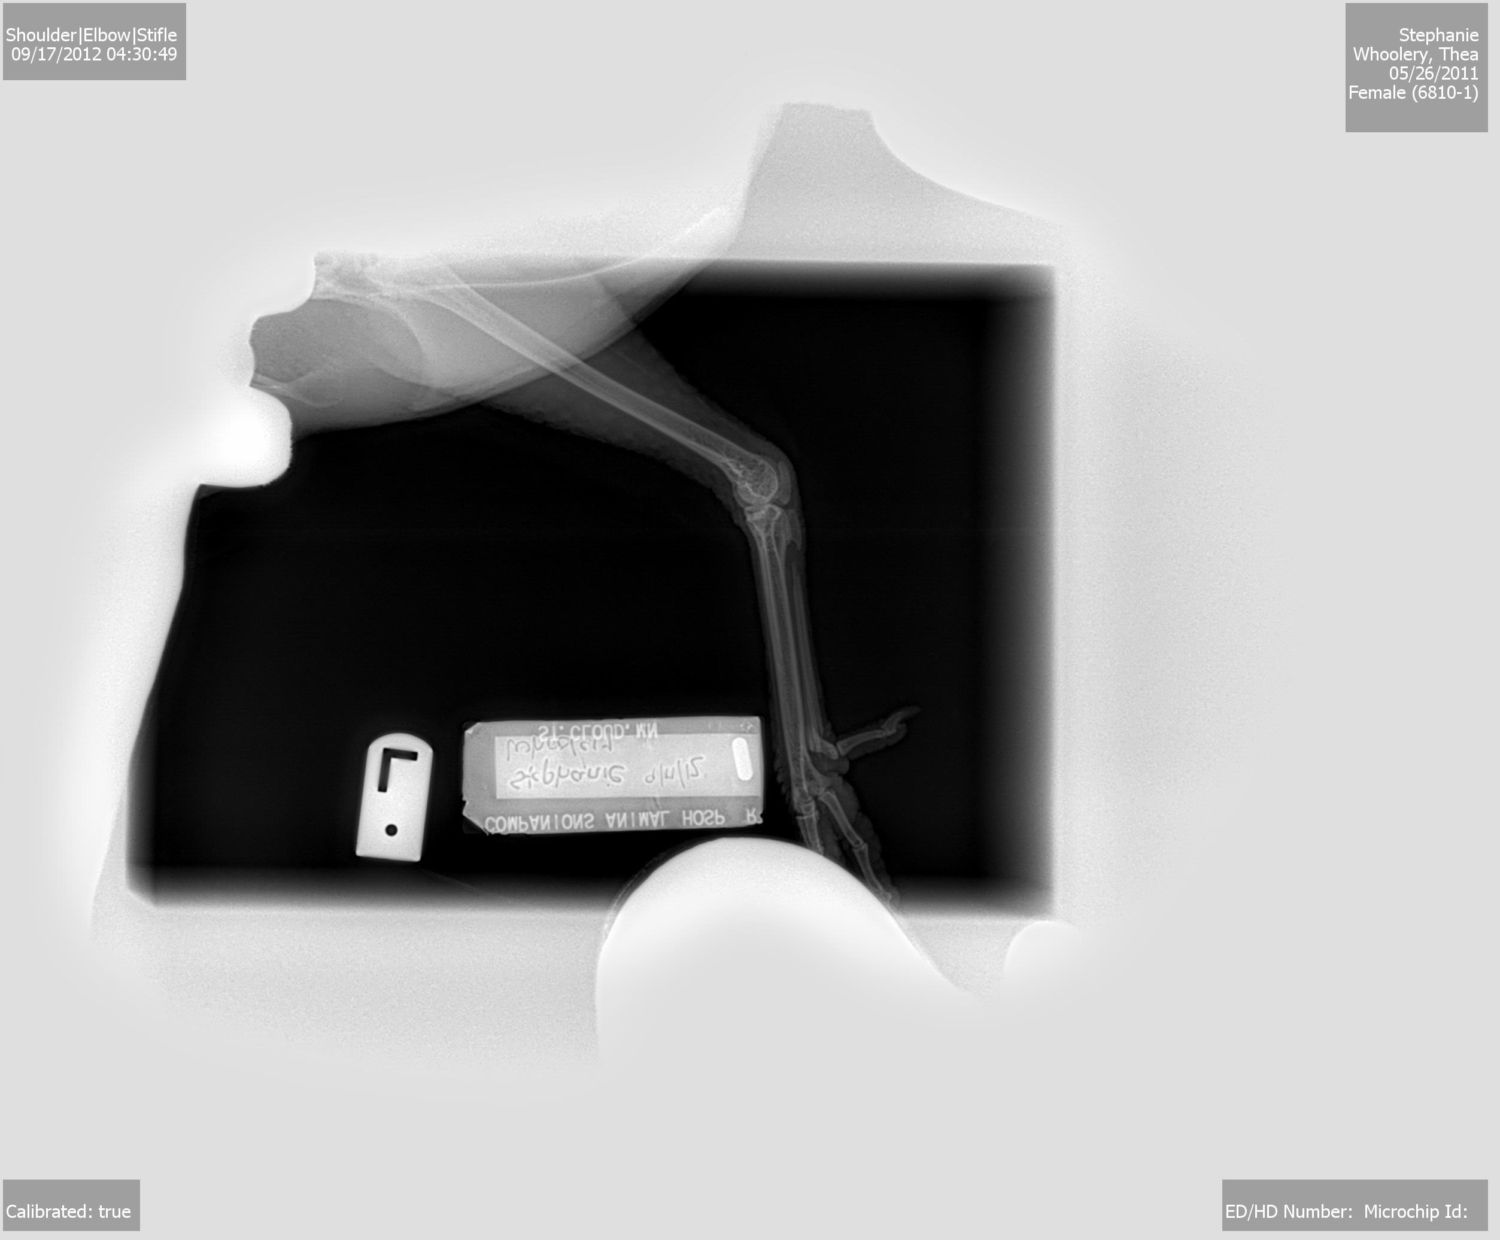

Took some xrays and everything looked good, not even swelling. We did a quick laser therapy session to hopefully help her out (was only like 20 bucks, whatever)

She honestly didnt know what it is around the knee.... she said she was going to look more into it and call me in a couple days to see how it was going...